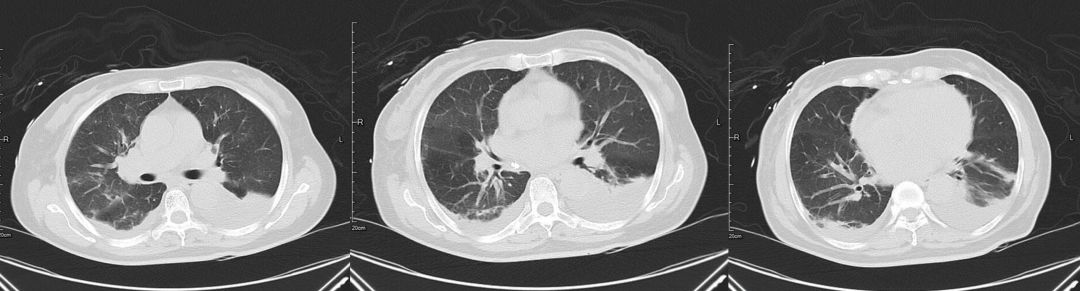

治疗后(2019-03-08)

患者咳嗽、胸闷症状明显缓解,3天后复查胸部CT提示肺部渗出影较前明显吸收。

肿瘤细胞浸润间质所致,咳嗽、咳大量粘液性泡沫性痰,病理可以明确鉴别。该病例中影像学表现密度相对均匀,与大叶性肺炎相比密度稍低,应用加强利尿3天后肺内磨玻璃影迅速吸收,变化快,肺部感染一般需2周甚至更长时间才能吸收,从影像特点及治疗后的反应上来讲均不支持肺炎。

5、多学科会诊后,加强心衰方面治疗,患者临床症状明显缓解,且胸部影像学短期较前相比明显吸收。后期复查心超发现赘生物,需进一步外科干预,因患者合并脑出血,暂缓手术,予内科保守治疗。